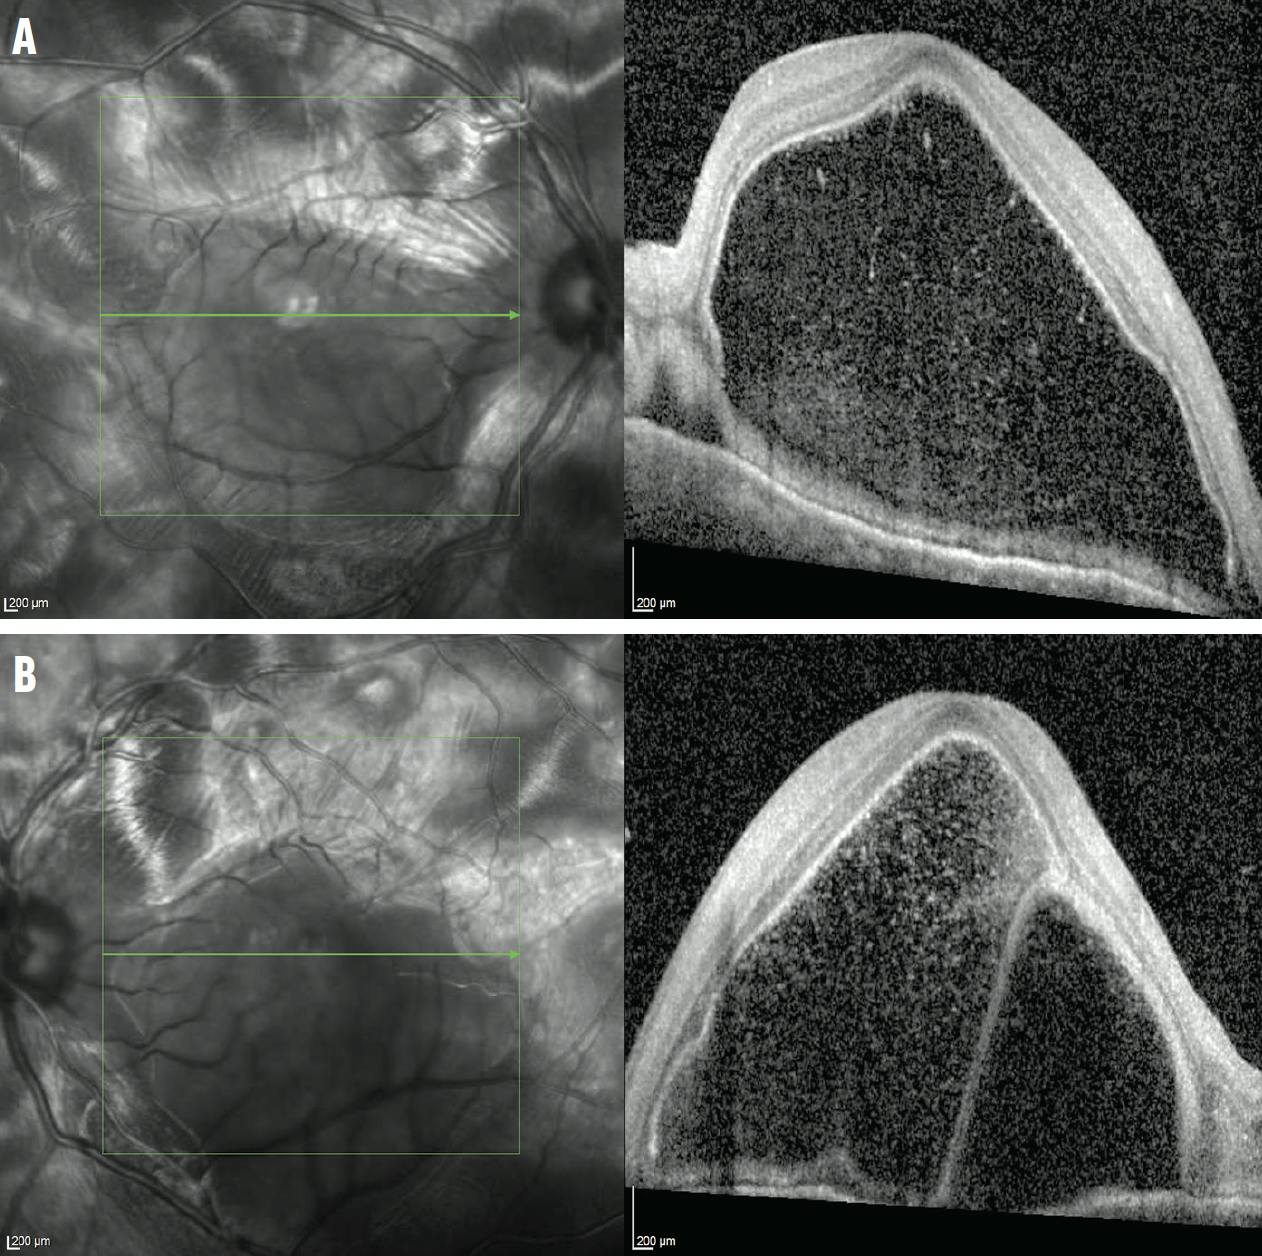

<p>Figure 3. OCT macula of the right (A) and left (B) eye showed small, bilateral bullous retinal detachments.</p>

Figure 3. OCT macula of the right (A) and left (B) eye showed small, bilateral bullous retinal detachments.